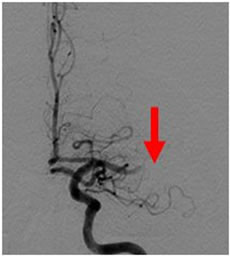

2例目を紹介いたします。81歳女性、自宅にて意識がなく、倒れているところを発見されました。来院時、JCS200と重篤な意識障害、左共同偏視、右片麻痺を認めました。頭部MRIにて脳幹に淡い梗塞、(図1)MRAにて脳底動脈の閉塞を認めました。(図2)再開通しなければ、死亡率が高い病態です。緊急にて血管撮影を行い、脳底動脈の閉塞を認めました。(図3)Penumbra吸引カテーテルと血栓除去用ステント(Trevo provue 4×20mm)を用いて血栓除去を行い、TICI3の完全再開通を認めました。(図4)翌日のMRIでは脳幹に梗塞を認めるも、(図5)意識障害は急速に改善しました。超高齢なために、約2ヶ月間のリハビリテーションを経て自宅へ戻りました。

図2:矢印のように、脳底動脈の描出が見られません。 |

図3:右椎骨動脈撮影です。矢印のところで脳底動脈は閉塞しています。 |